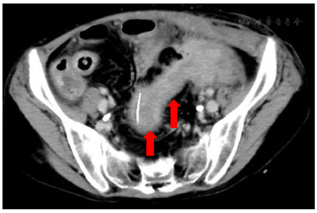

实验室检查:白细胞计数9.2×109/ L,中性粒细胞88.3%,血红蛋白56 g/L,降钙素原124 μg/L,白蛋白22.1 g/L,前白蛋白20 mg/L。消化道道造影提示,经肛门注入造影剂,可见只有直肠中下段显影良好其余结肠显示不清,广泛结肠及直肠炎,回盲部也受累(图1)。经外瘘口注入造影剂,见左盆腔不规则脓腔显影(图2)。骨密度检测提示骨质疏松。